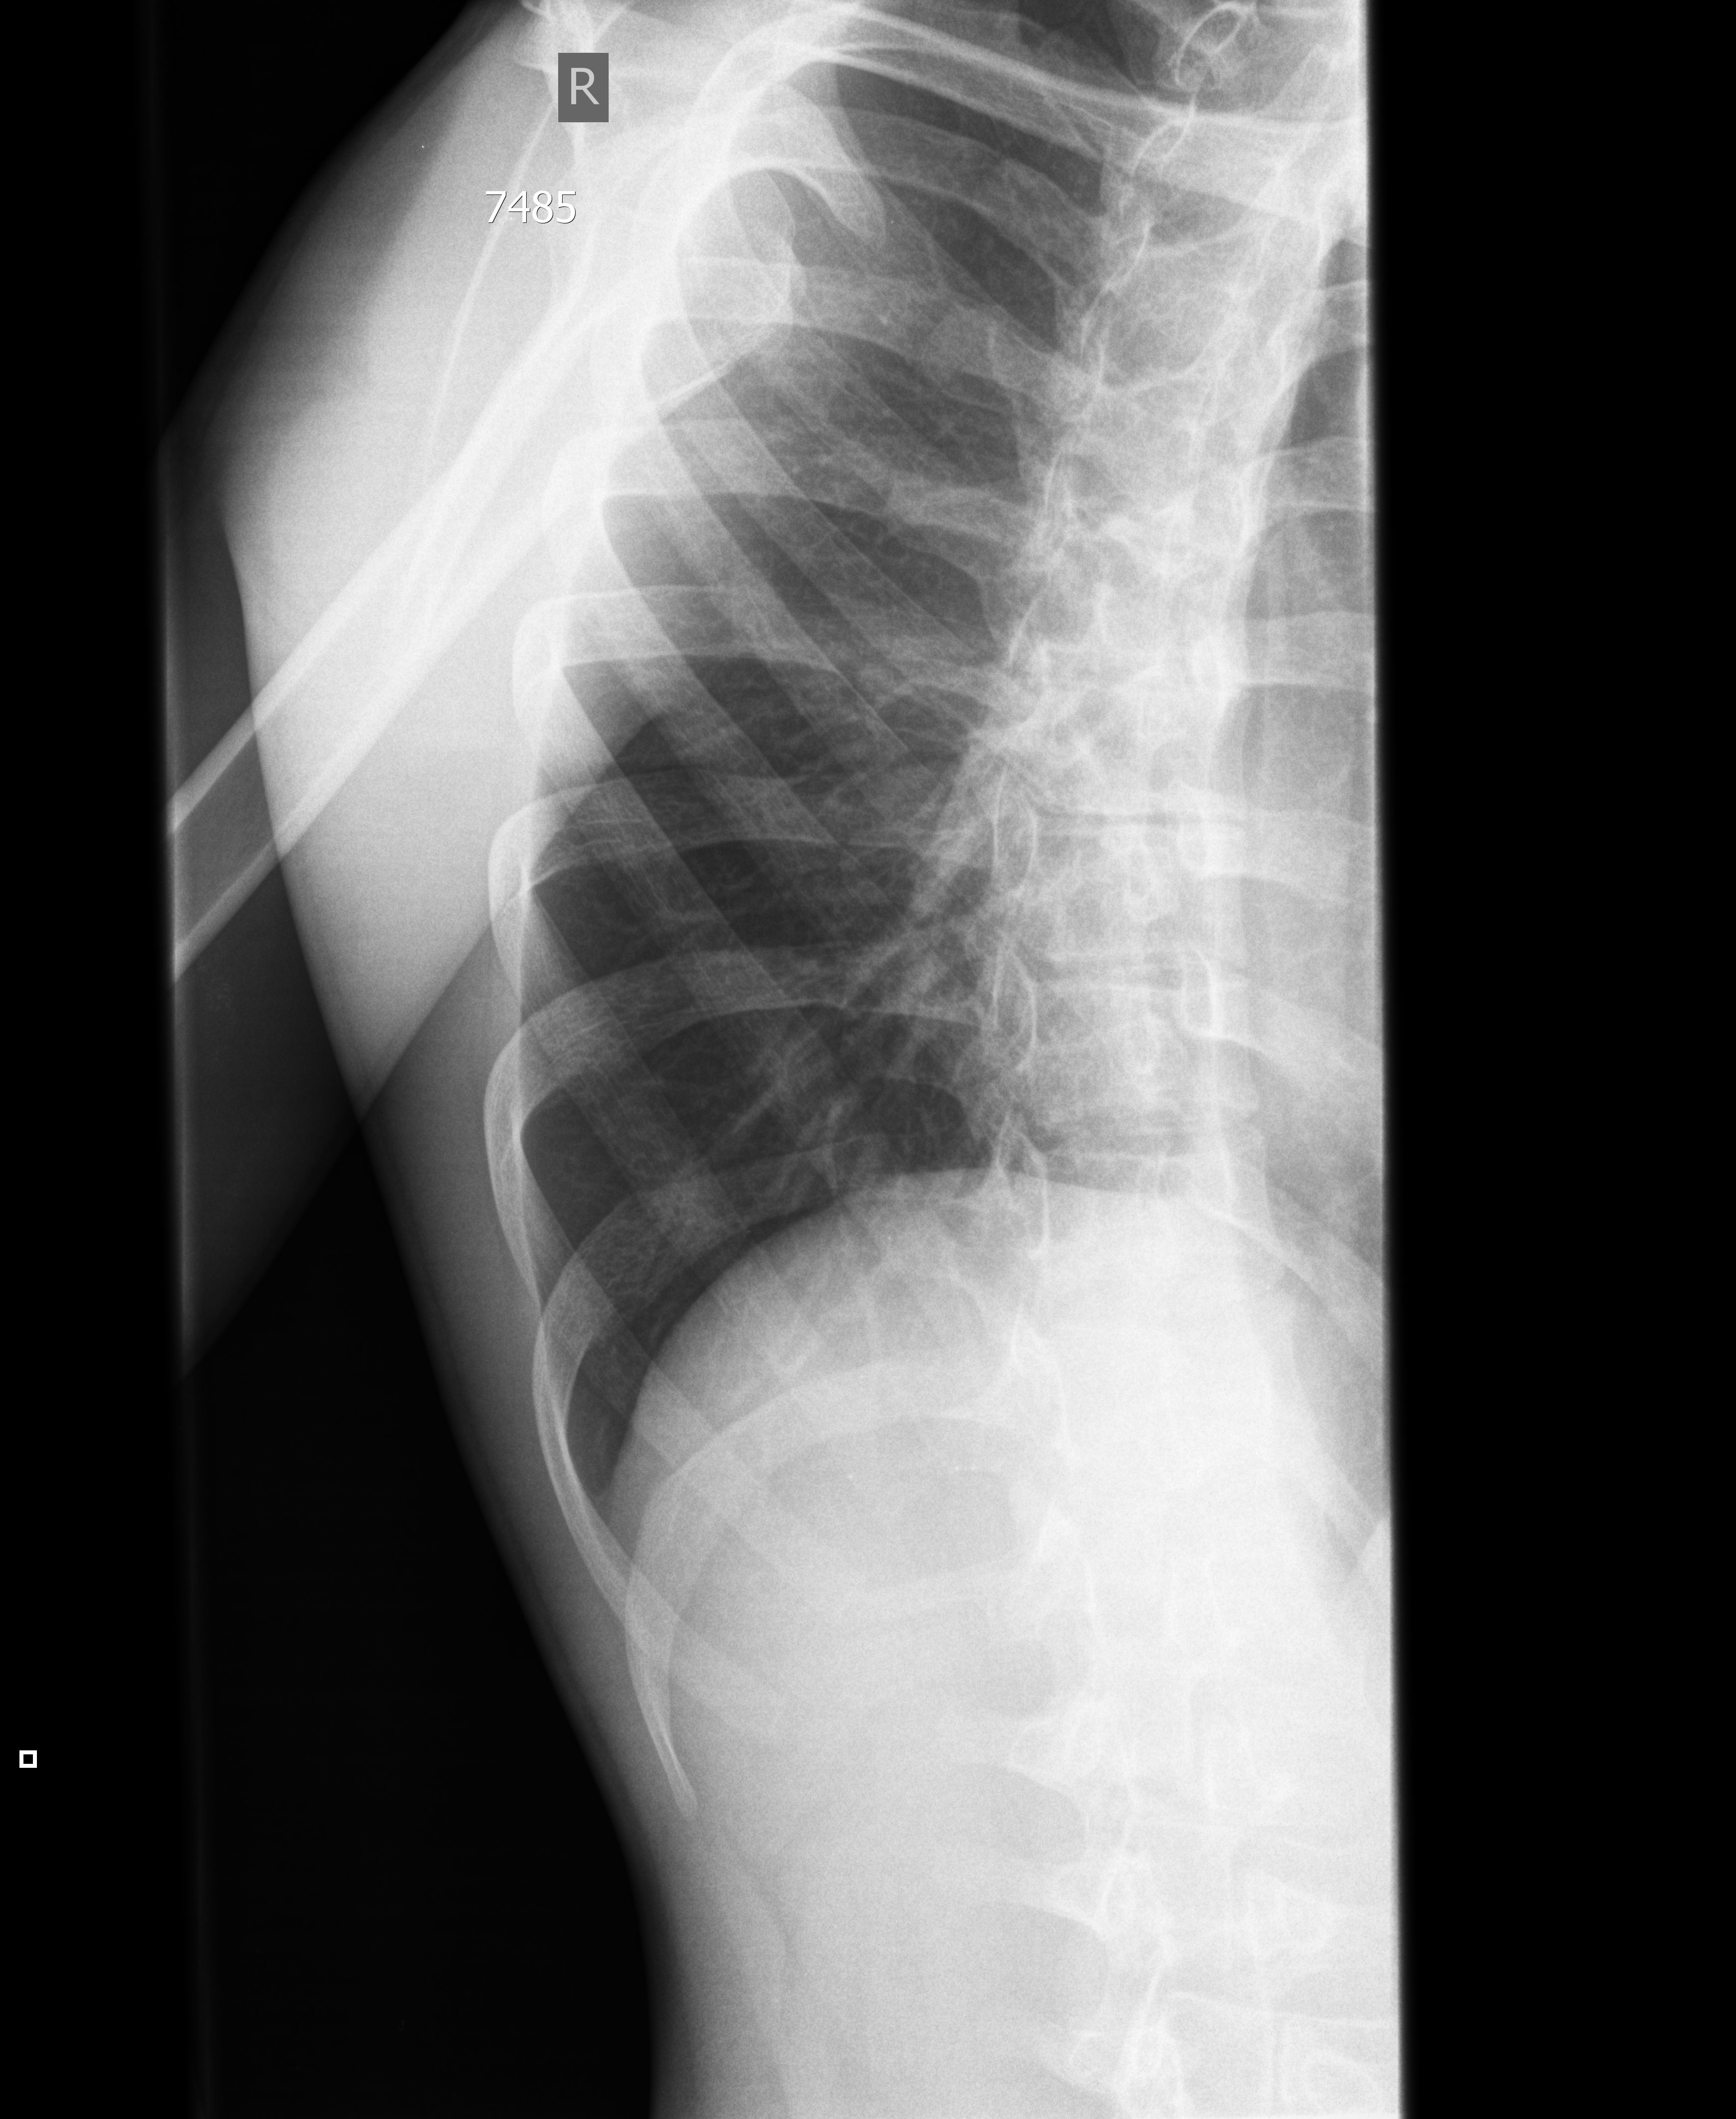

19y M

RGuyuasydf1.jpg